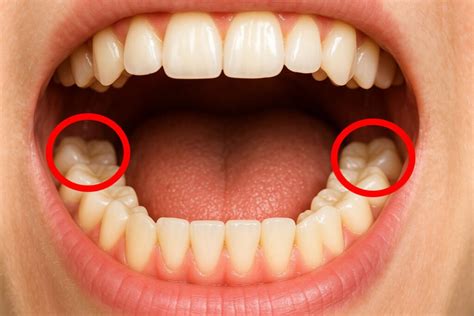

Ubicación de las Muelas del Juicio

Las muelas del juicio salen en la parte más posterior de la boca, justo detrás de los segundos molares o muelas grandes que ya tenemos desde la adolescencia. En cada lado de la mandíbula hay una muela del juicio arriba (en el maxilar superior) y otra abajo (en la mandíbula inferior). Son, por así decirlo, las “últimas de la fila” en la arcada dentaria.

En mi experiencia, muchos pacientes no se dan cuenta de la erupción hasta que la muela del juicio ya está presionando la encía o al diente vecino. Esto se debe a que suelen estar “escondidas” bajo la encía durante buena parte de su desarrollo.

Algunas muelas del juicio logran erupcionar completamente (es decir, salir del todo a través de la encía) y alinearse correctamente con el resto de los dientes. Sin embargo, es muy común que no tengan suficiente espacio para salir del todo.

Nuestras mandíbulas actuales suelen ser más pequeñas, así que el “hueco” al fondo no siempre alcanza. Por eso, muchas muelas del juicio quedan parcialmente erupcionadas (asomando solo una parte) o retenidas debajo de la encía o contra el hueso. Más adelante explicaré los problemas que esto puede acarrear.